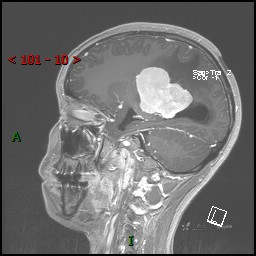

视物模糊发现颅内占位,“豆蔻年华”却承受开颅之痛,所幸一切顺利---结果公布~

患者年龄:14岁

简要病史:患者于1月前无明显诱因出现视物模糊,无明显头痛头晕,无恶心呕吐,无昏迷,无肢体偏瘫等症状,就诊于当地医院头部CT考虑:右侧丘脑、脑室占位。予以对症处置后家属为求进一步诊治来我科,以“颅内占位”收入院。 起病以来,精神、饮食、睡眠欠佳,大小便正常,体力下降,体重无明显变化。

临床诊断:脑室占位

MRI平扫